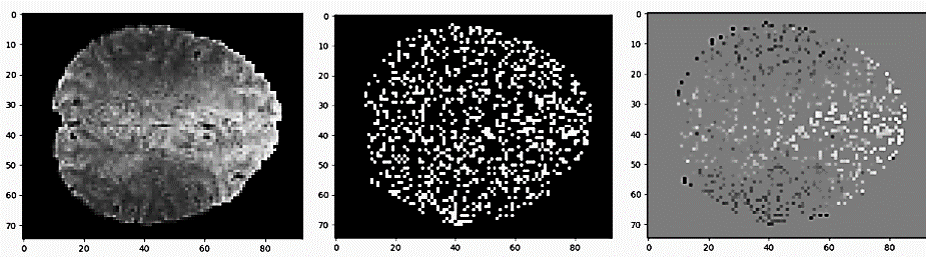

The second loss is an intensity loss, denoted as . This loss is based on an L1 applied to a subset of the voxels associated with local intensity values, which are more likely to represent a relevant BOLD signal. More specifically, given a full scan, , we infer the voxel-normalization . Then, for each voxel-normalized frame , we set if and otherwise, where is a threshold value configured as the 80% quantile of the absolute of the voxel-normalized values, inside the anatomy and across the sub-sequence. The motivation behind the elimination of the voxels associated with the 80% of the values that are closer to 0 is that these values are typical across many frames, and are therefore unlikely to represent a distinctive signal. An illustration of the intensity loss is depicted in Fig. 5 in the supplementary appendix.

The intensity loss is based on an L1 loss applied to a subset of the temporally-intense voxels, which are more likely to represent a relevant BOLD signal. The intensity loss eliminates voxels associated with 80% of the values that are close to 0 were eliminated since they are typical across many frames and are therefore unlikely to represent a distinct signal. A representative slice and its voxels associated with the intensity loss can be seen in Fig. 3.